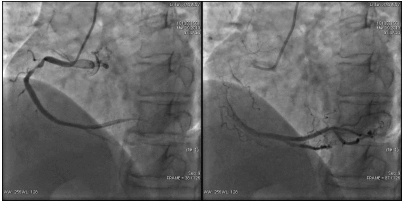

第一次手术过程

手术时间: 入院第19天。

术中用药: 术中追加肝素4000单位。

手术过程: 于LCX、RCA植入支架两枚。效果良好,未见残余狭窄,TIMI血流3级。

![]()